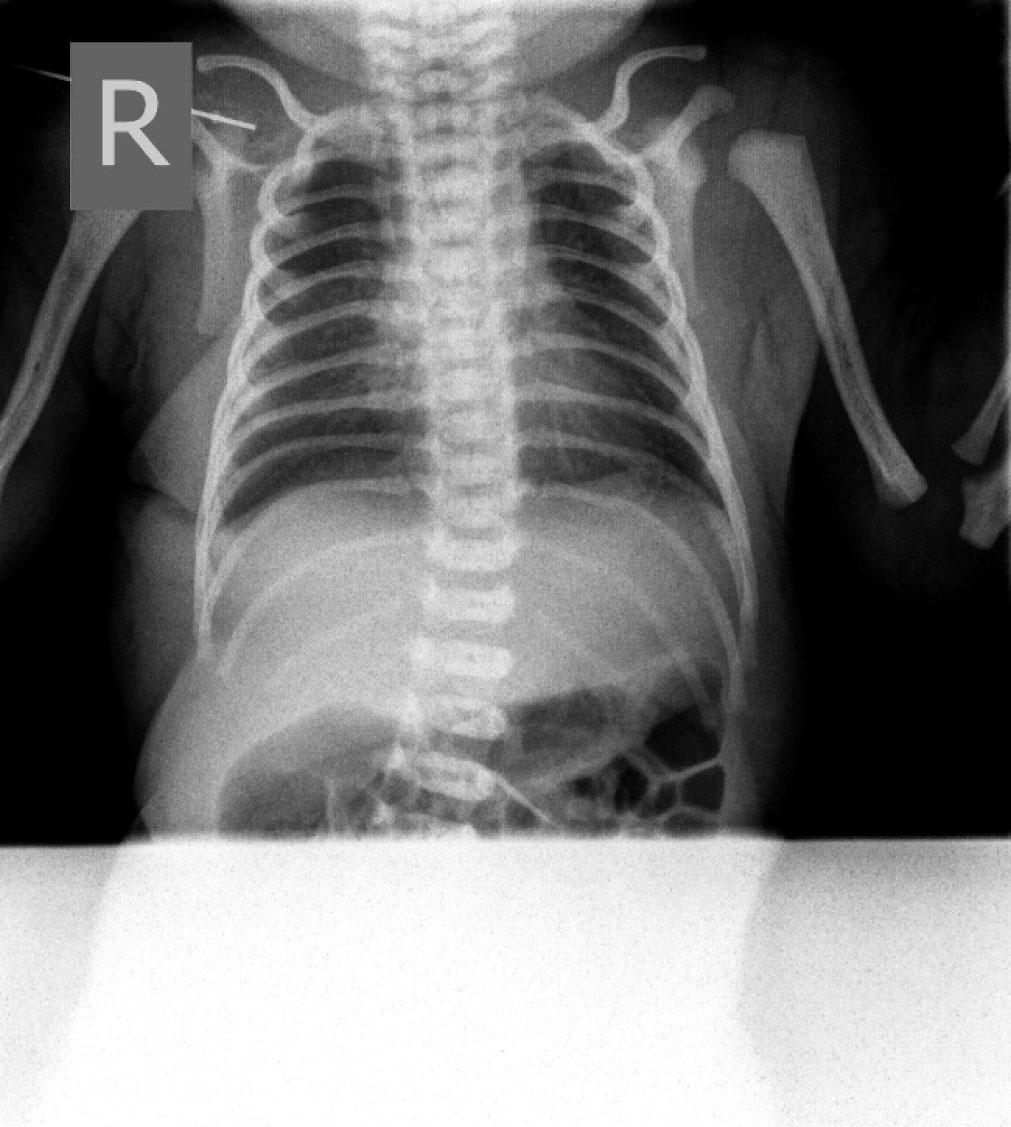

A chest radiograph after resolution of pneumopericardium and pneumothorax

A term male infant, weighing 2700 grams at birth, was born at 39 weeks to a healthy mother (blood type O, Rh positive) delivered spontaneously by vaginal route. Pregnancy was well monitored and unremarkable. The infant cried immediately after birth and did not require any interventions. He had a birth weight of 2700 grams, a length of 52 cm and a head circumference of 34 cm. Apgar scores were 9 and 9 at 1th and 5th minutes, and infant was transferred to the postnatal unit with his mother for regular postnatal care. During the third hour of age, his skin started to become diffusely livid with evidence of respiratory distress, tachypnea (respiratory rate = 63/min) and heart rate 136/min. He was transferred to the neonatal intensive care unit (NICU) for investigation and further management. On admission, his vital signs showed a temperature of 36.6 °C, heart rate of 101 per minute and respiratory rate of 68 per minute. His blood pressure was 77/50 mmHg and his weight reduced to 2680 grams. Capillary blood gas analyzed on a Gem Premier 3000 gas analyzer showed pH 7.05; PaCO2 13.1 kPa; PaO2 2,4 kPa; bicarbonate 27.1 mmol/l; base excess of −3,4 and SaO2 84%. Nasogastric tube was placed. The chest examination showed chest retraction as compared with abdominal retraction during inhalation – 2 points; retraction of the lower intercostal muscles – 1 point; xiphoid retraction – 0 points; flaring of the nares with inhalation – 1 point; grunting on exhalation – 1 point, suggesting Silverman score = 5 points which indicates moderate respiratory distress. In view of his respiratory distress, the infant remained in the incubator and hood with 40% fraction of inspired oxygen (FiO2) was applied and 20 mg of Theophylline (Aminophylline®) given 5mg/12hours. A chest radiograph revealed bilateral apical pneumothorax in Figure 1. A chest drain was placed between anterior and midaxillary line in the 5th right intercostal space. The procedure was done in aseptic conditions after the area was cleaned with 0.015% chlorhexidine and spontaneously dried for half a minute. A dose of 0.3ml/kg of 1% lignocaine was subcutaneously applied. An incision was made using a sterile scalpel above the inferior rib. An incision place was carefully pinpointed to avoid a well-known location of important neurovascular structures right below the superior rib. The chest drain was fixated using two sterile surgical stripes. The secondary capillary blood gas analysis showed pH 7.10; PaCO2 10.4 kPa; PaO2 3,4 kPa; bicarbonate 24.2 mmol/l; base excess of −5,5 and SaO2 was 89%. The following day radiological signs of bilateral partial pneumothorax showed mild signs of resolution. Blood gas analysis on showed pH 7.35; PaCO2 5.5 kPa; PaO2 3,8 kPa; bicarbonate 22.6 mmol/l; base excess of −3 and SaO2 was 94%. The next morning the infant had tachypnea and dyspnea with SaO2 89%. Cardiovascular examination showed muffled heart sounds with no audible murmur and heart rate 123 per minute. Chest X-ray showed complete resolution of pneumothorax however classical ‘Halo’ sign appeared, (a collection of air surrounding the heart in the pericardial sac) indicating existence of pneumopericardium, which can be seen in Figure 2. The infant became acidotic and SaO2 dropped to 83%. Due to inadequate fixation of the chest drain, it spontaneously moved and may have damaged the pericardial sac. Along with the already existing pneumothorax, probably a combination of ventilation mechanism and trauma resulted in air leak into the pericardial sac. The chest drain was therefore repositioned (extracted by 3 centimeters) and due to possible progression to life threatening cardiac tamponade the infant had to be closely observed with cardiorespiratory monitoring and series of chest radiographs. Over the course of next 24 hours the clinical and radiographical signs of pneumopericardium resolved. Respiratory rate was 42 per minute and heart rate was 115 per minute. SaO2 was 96%. Thoracal drain was then removed and latter subsequent chest radiographs showed no recurrence of either pneumothorax or pneumopericardium (Figure 3). The infant remained in incubator under diffuse oxygen therapy with FiO2 40% and in the following 48 hours his oxygen requirement was weaned gradually to room air and was discontinued the next day. He was discharged on 8th day of his life. His regular follow-ups showed he was thriving well.